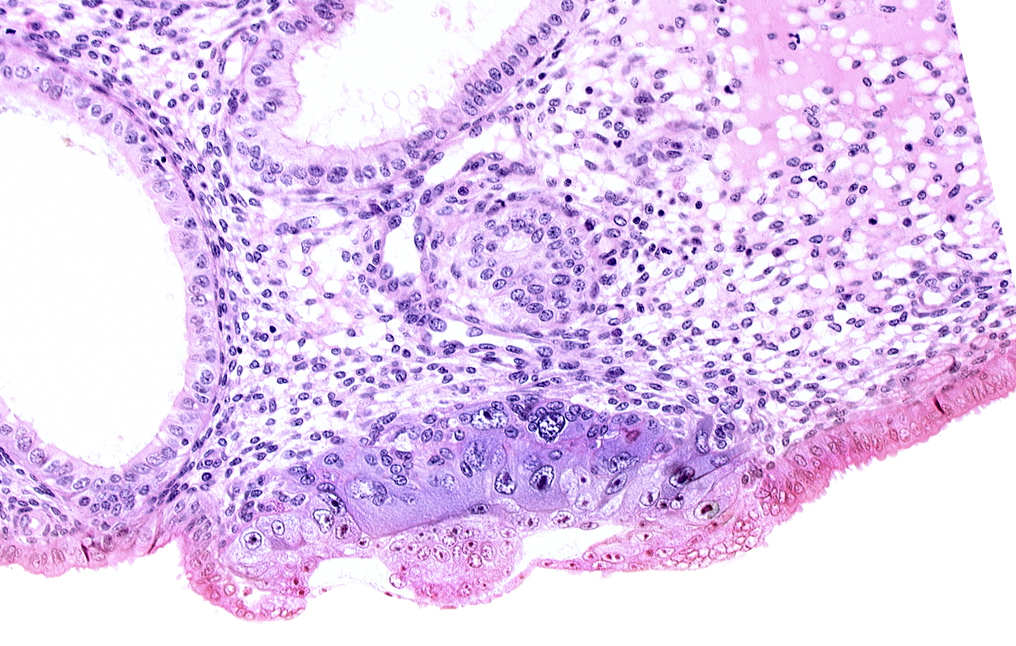

Carnegie Embryo #8020 | Location: 06-02-04

Keywords: blastocystic cavity (blastocoele), endometrial epithelium, endometrial sinusoid, epiblast, hypoblast, membranous trophoblast at abembryonic pole

Source: The Virtual Human Embryo.